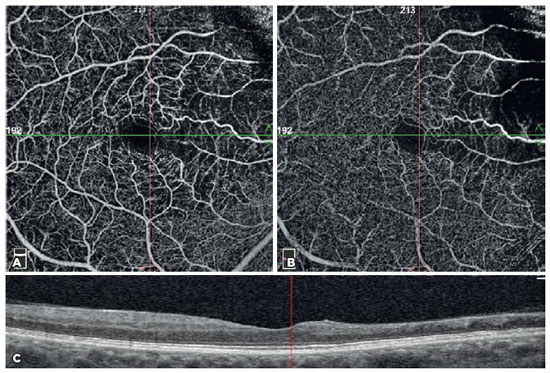

The software (Version 2017.1.0.151) automatically inserted three fovea-centered circles on the macula. The density of the foveal zone vessel was defined as the area of the small circle, with a diameter of 1 mm. The density of the parafoveal zone vessel was defined as the area of the middle circle, with a diameter of 3 mm. The density of the perifoveal zone vessel was defined as the area of the outer circle, with a diameter of 6 mm. In addition, the parafoveal zone was automatically divided into four equal quadrants (i.e., temporal, nasal, inferior, and superior) and two equal hemispheres (i.e., superior and inferior) (Figure 2).

06-fig02tb.jpg)